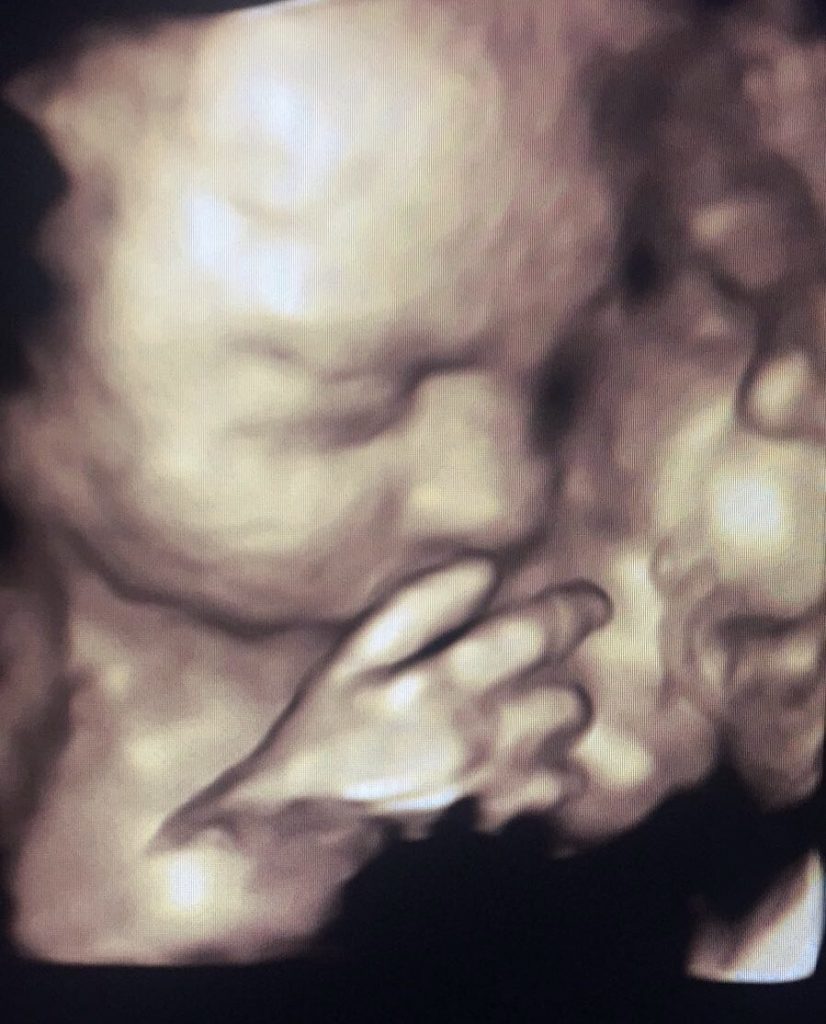

Baby scan image 3